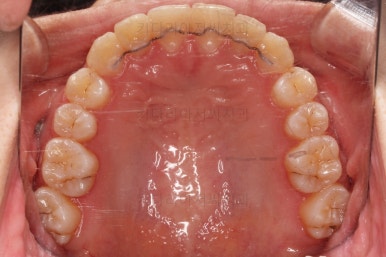

입 안을 보면 밑에 치열이나 다른 부분은 비교적 양호한데 유달리 윗니 송곳니만 위치가 좋지 못하네요.

충치가 곳곳에 보이는데요.

성인들은 충치가 멈춰있는 정지우식일 가능성도 있으며 크기가 현재 크지 않고 향후 변화되지 않는다면 그대로 두기도 합니다.

이번 환자분도 교정치료에 방해되는 부분이나 급해보이는 추료만 우선 진행하고 교정 중에 충치가 커지는지 증상이 생기는지 관찰해 보기로 했습니다.